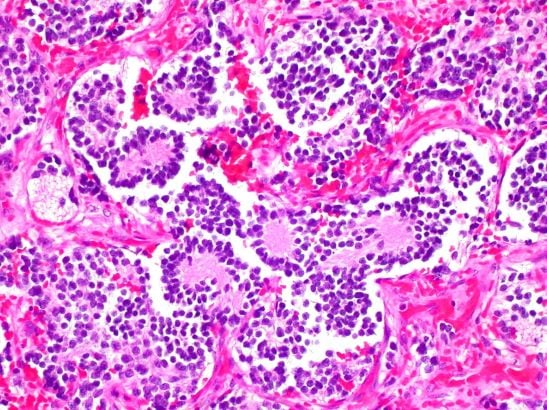

Image: Neuroblastoma of the adrenal gland. Credit: Ed Uthman. CC BY-NC 2.0